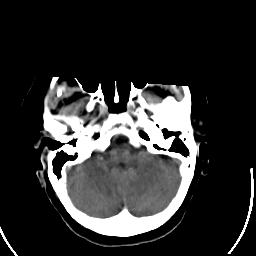

Stroke CT #2 -- Slice #4

[Home][Help][Clinical] Slice 4